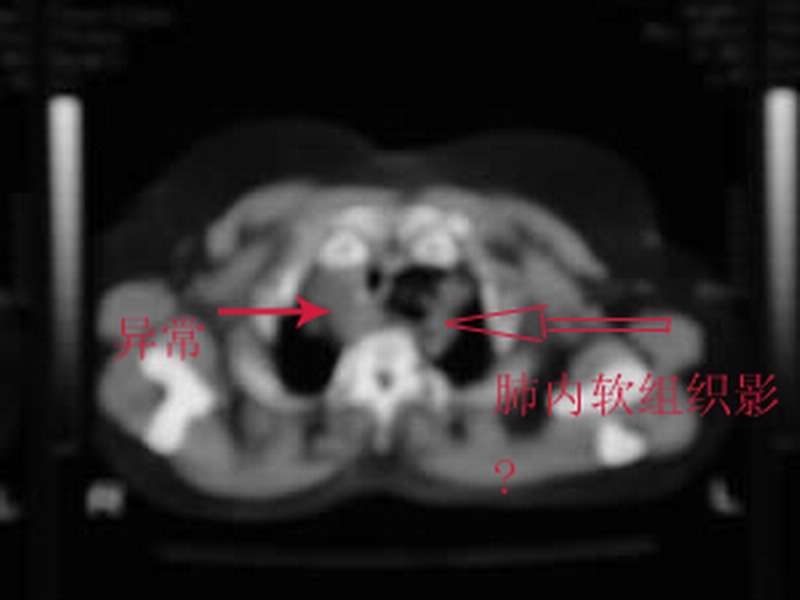

上纵隔气管左旁是脂肪密度吧,似有片状软组织影,畸胎瘤?

纵隔气管左旁是脂肪密度吧,似有片状软组织影,畸胎瘤?

上纵隔气管左旁是脂肪密度吧,似有片状软组织影,气管约右移,考虑---1畸胎瘤。2脂肪瘤或局部脂肪沉积。

似乎起源于甲状腺,顺气管向下爬行

支持-- 上纵隔气管左旁是脂肪密度吧,似有片状软组织影,气管略右移,考虑---1畸胎瘤。2脂肪瘤或局部脂肪沉积。